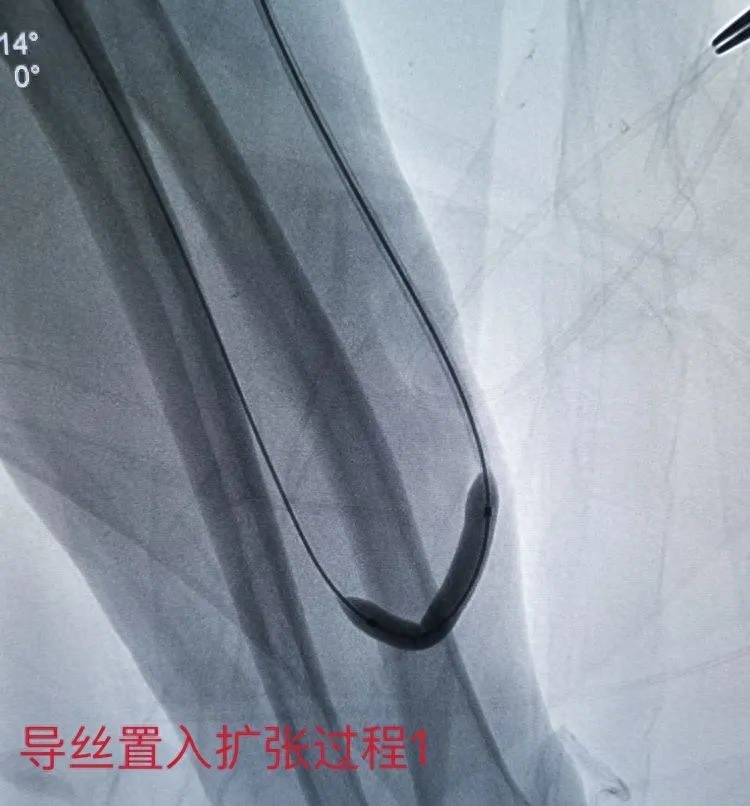

手术开始,专家采用导丝引导5F单弯导管选入头静脉吻合处,造影见头静脉内多发血栓形成、多发狭窄病变,局部可见重度狭窄及扩张段。

手术中,曾庆福博士和刘志华医师耐心继续置入导丝,利用穿刺鞘反复负压抽吸血栓,采用高压球囊扩张对狭窄处继续逐段扩张。